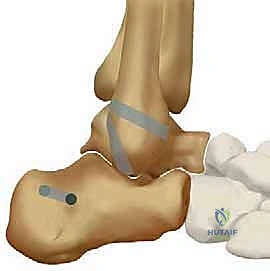

هذه هي الخطوة الأكثر دقة وتتطلب خبرة عميقة في الميكانيكا الحيوية للكاحل. يقوم الدكتور هطيف، بناءً على المعالم التشريحية الدقيقة، بحفر أنفاق في العظام في المواقع الأصلية (Isometric points) للأربطة الممزقة:

* نفق في عظمة الشظية (Fibula).

* نفق في عظمة الكاحل (Talus) لتعويض رباط ATFL.

* نفق في عظمة الكعب (Calcaneus) لتعويض رباط CFL.

الخطوة الرابعة: تمرير الطعم وتثبيته (Graft Passage and Fixation)

يتم تمرير الطعم الذاتي (وتر الرشيق المُجهز) عبر الأنفاق العظمية بمسار يحاكي تماماً المسار الطبيعي للأربطة (ATFL و CFL). هذه التقنية التشريحية تضمن استعادة الحركة الطبيعية للكاحل دون تقييد.

يتم بعد ذلك تثبيت الطعم بقوة داخل العظام باستخدام براغي تداخلية (Interference Screws). هذه البراغي مصنوعة من مواد حيوية متقدمة (Bio-absorbable أو PEEK) تندمج مع العظم بمرور الوقت. يتم شد الطعم بالدرجة المناسبة (Tensioning) بينما تكون القدم في وضعية محايدة لضمان أقصى درجات الثبات.